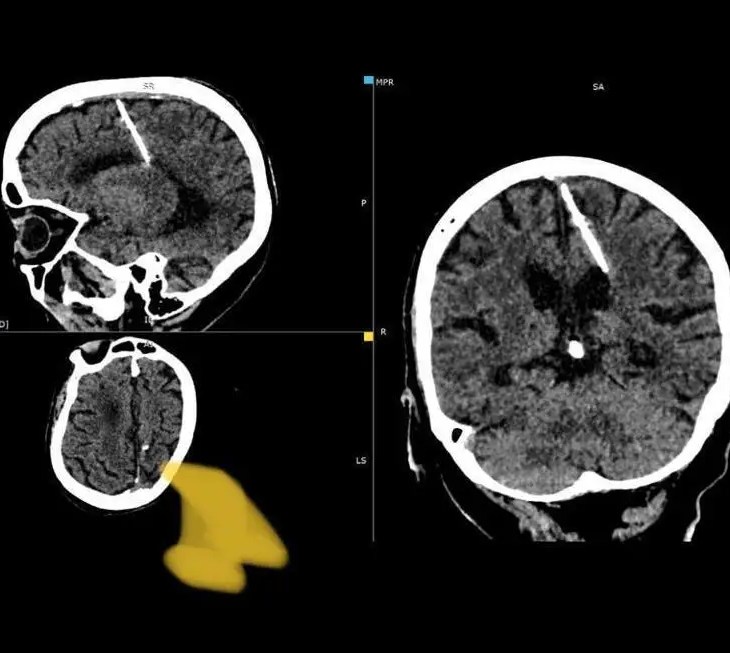

Elderly Russian Woman Found Living With A Needle in Her Brain

By Staff During a startling revelation, doctors in Russia’s far east discovered a 3 cm-long…